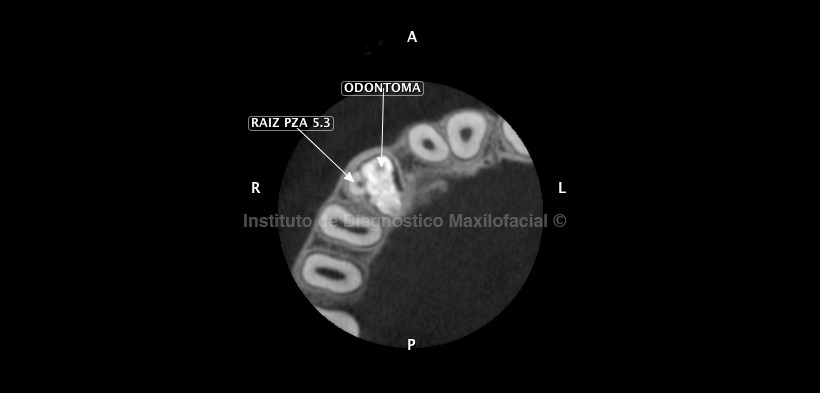

En los cortes axiales nos muestra la lesión orientada hacia vestibular y en íntima relación con la raíz de la pieza 5.3 además de la presencia de múltiples estructuras de apariencia dentaria de diversas formas y tamaño (Fig. 3), produciendo la divergencia radicular de esta. Así mismo, también presenta estrecha relación con el espacio folicular de la pieza 1.3 (Fig. 4 y 5), el cual se encuentra ligeramente aumentado de tamaño.